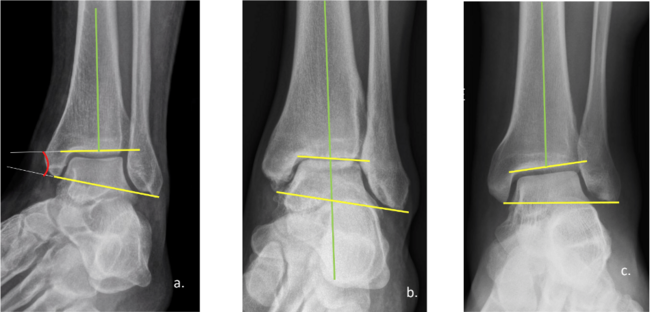

Case #2. In this case, a 35-year-old male soldier presented with chronic ankle instability and a previous Haglund’s deformity. X-rays clearly show an ankle in significant valgus, but his weight-bearing foot X-rays show a foot inverting to compensate for the ankle valgus (click here for Figure 4). Ultimately, I find that one can’t just address the instability without a tibial osteotomy (click here for Figure 5). In this case we performed a closing tibial osteotomy, secured the osteotomy with a single, 6.5mm cannulated screw. One can also choose to utilize a medial plate (click here for Figure 6).